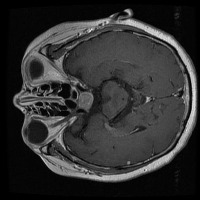

tumor otak Computer Vision Project

Here are a few use cases for this project:

Medical Diagnostics: This model can be used for assisting healthcare professionals in diagnosing brain tumors by classifying them into glioma, pituitary, or meningioma, which can save time and lead to early and accurate disease diagnosis.

Health Monitoring Software: It can be implemented in health and wellness apps to monitor a patient's MRI scans regularly, thus providing an early warning system for possible tumor growth.

Training medical students and resident doctors: The model can be used as a training tool for medical students and resident doctors to better understand and identify different types of brain tumors from MRI images.

Research Studies: It may be used by scientists and researchers for creating more focused and comprehensive studies on brain tumors, contributing to advancements in the respective field of study.

Telemedicine: This model can be helpful in telemedicine portals where expert opinion may be lacking. The model could provide initial diagnosis based on MRI scans before a patient consults with a healthcare professional.